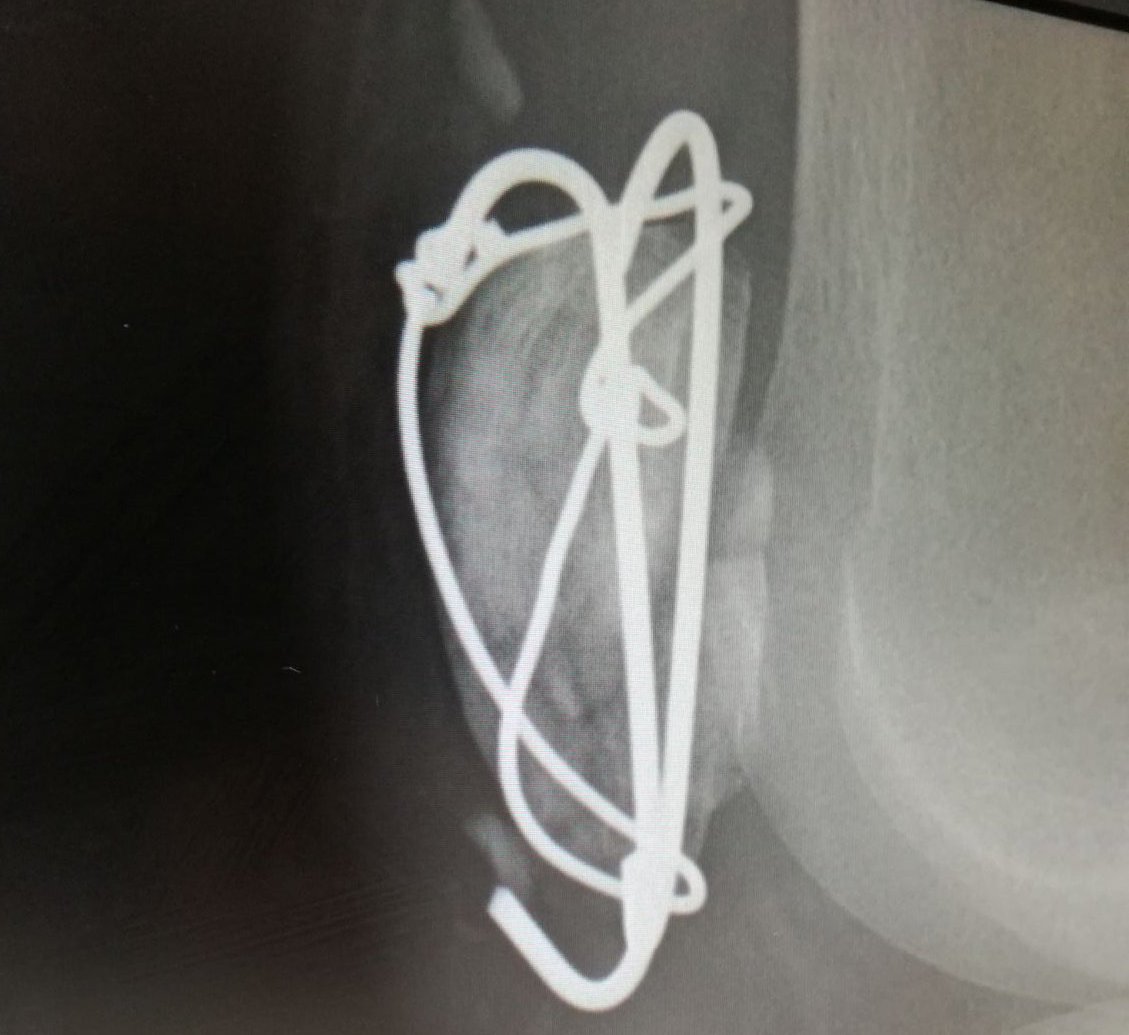

On Tuesday 24th I'll have all this metal removed, keyhole camera surgery and cartilage removal.

Fingers crossed this is the path to 100% recovery